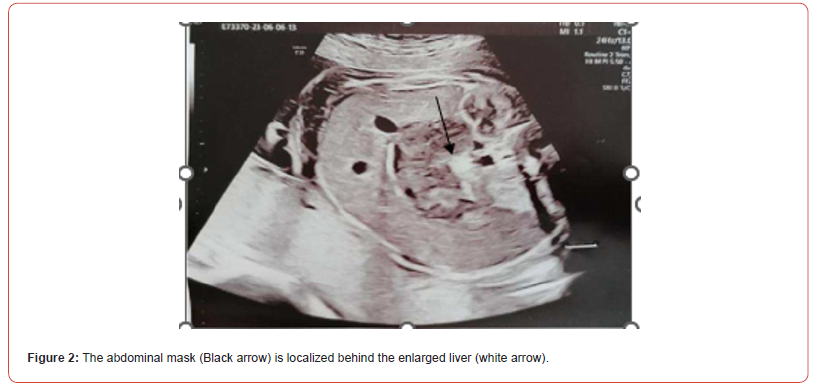

A 37 years-old pregnant woman, gravida 2 para 2, was referred to our hospital by her Gynaecologist for fetal abdominal and pericardial effusion at 35 4/7 weeks. Up to this point her pregnancy was eventful for a diagnosis of gestational diabetes with unremarkable ultrasounds up until the third trimester when the fetal stomach could not be visualized. Fetal growth was at the highest percentiles and amniotic fluid levels were normal. Our ultrasound showed subcutaneous oedema mostly at the abdomen (10 mm) and prefrontal space (8.5 mm), mild intra-abdominal fluid (5.4 mm) and a tubular abdominal mass moderatly vascularized with Color-Doppler with a disomogeneous echogenicity similar to the echogenicity of a clot with no peristaltic movements (Figure1,2). Fetal stomach cound not be visualized and amniotic fluid levels were normal. The ultrasound also showed reduced active fetal movements. Given the initial signs of fetal distress and the accomplished gestational age, it was decided to expedite the delivery via C- section. A female fetus was delivered, with meconium-stained amniotic fluid grade 1. In the delivery room she was ventilated due to bradycardia and apnea and subsequently intubated for the persistence of apnea. Apgar score was 3-6-7 respectively at 1’, 5’ and 10’ minute of life. Cord arterial blood gas showed anemia with 20% haematocrit and normal acid/base status. The birth weight was 2800 gr (84th centile). The baby persisted hypotonic, hyporeactive, pale, presented diffuse subcutaneous oedema and firm violaceous diffuse (face, thorax, limbs) cutaneous lesions (papules and nodules) suspicious for cutaneous metastasis (blueberry muffin baby). Palpation of the abdomen revealed a soft, non-tender, middle-abdominal mass and splenomegaly. She was then transferred to the NICU and underwent an urgent abdominal ultrasound showing: a diffusely hypoechoic voluminous mass (2,2 cm thickness) in the pancreatic space with echoic areas in its context and marked vascularization by mesenteric vessels without vessel compression. Splenomegaly with bipolar lenght of 7,4 cm with heterogeneous echotexture and hypoechoic triangularshaped areas in the subcapsular space. Transfontanellar Cerebral Ultrasound and Echocardiography Showed No Alterations.